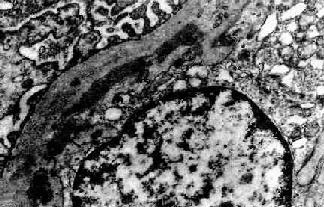

图12-13 膜性增生性肾小球肾炎

肾小球系膜细胞增多,增生的系膜组织侵犯毛细血管,毛细血管壁增厚,腔狭小,肾小球丛呈分叶状

图12-15 膜性增生性肾小球肾炎 Ⅰ型

肾小球毛细血管基底膜内侧,内皮细胞下电子致密沉积物,部分上皮细胞足突消失